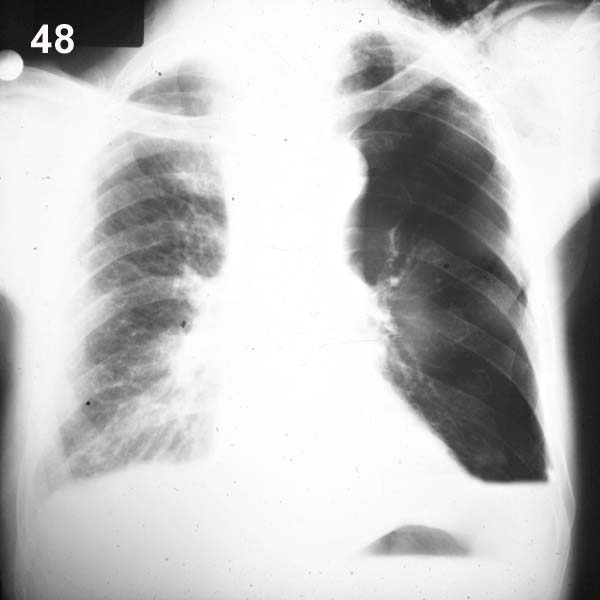

| ESQUEMA 48

Comentario placa 48 Además de una amplia cámara de neumotórax al lado izquierdo se observa en la base de este hemitórax una sombra homogénea de límite superior horizontal. Se trata de un neumotórax con acumulación de líquido pleural o hidroneumotórax. Por en la gran cámara del neumotórax una interfase aire-líquido, se produce un límite horizontal muy neto (imagen hidro-aérea). |